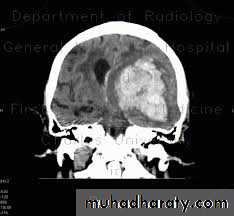

Structural- Supratentorial

Traumatic

Vascular

Inflammatory

Neoplastic

Brain Herniation

Supratentorial herniation

• Uncal (transtentorial)• Central